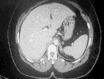

Introduction: Liver rupture is a serious event that is most commonly due to blunt abdominal trauma. We present a case of peliosis hepatis in a patient admitted for acute pyelonephritis who developed hemoperitoneum due to spontaneous hepatic rupture from this rare liver condition.

Presentation of case: We report a 44 year-old woman who presented to our hospital with acute pyelonephrititis and hemoperitoneum due to spontaneous hepatic rupture from peliosis hepatis. Physicians should be aware of this rare condition in patients who present with non-traumatic hepatic rupture with hemoperitoneum.

Discussion: PH should be considered in all patients with known risk factors who present with typical morphological changes or a hepatic mass, especially when the cause of sudden intraperitoneal hemorrhage is obscure.

Conclusion: Peliosis hepatis is most often asymptomatic and an incidental finding at autopsy. In symptomatic patients, surgery should be reserved for those patients whose hemorrhage is-life-threatening. Familiarity with the imaging characteristics can help in earlier diagnosis of peliosis hepatis.